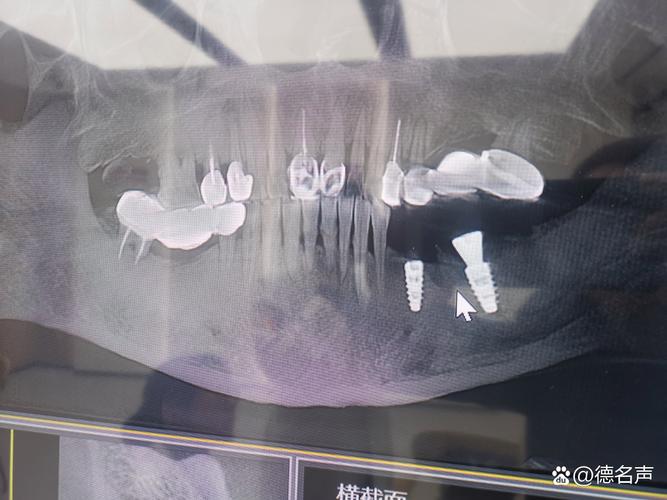

- 骨密度与骨量检测:采用双能X线吸收法(DXA)检测腰椎或髋部骨密度,明确骨质疏松程度(T值≥-1.0SD为正常,-1.0~-2.5SD为骨量减少,≤-2.5SD为骨质疏松);通过锥形束CT(CBCT)评估牙槽骨的骨量(高度、宽度)及骨密度(可通过Hounsfield值定量分析,骨密度值越低,骨质量越差)。

- 微创种植:采用数字化导板引导种植,精准控制种植位置、角度与深度,减少对周围骨组织的损伤;使用超声骨刀等设备进行骨切割,降低骨热损伤(骨温度超过47℃时会导致骨细胞坏死)。

- 定期复查:术后1、3、6个月复查种植体稳定性与骨结合情况,之后每年复查一次,通过CBCT观察种植体周围骨密度与骨吸收情况,及时发现并处理并发症。